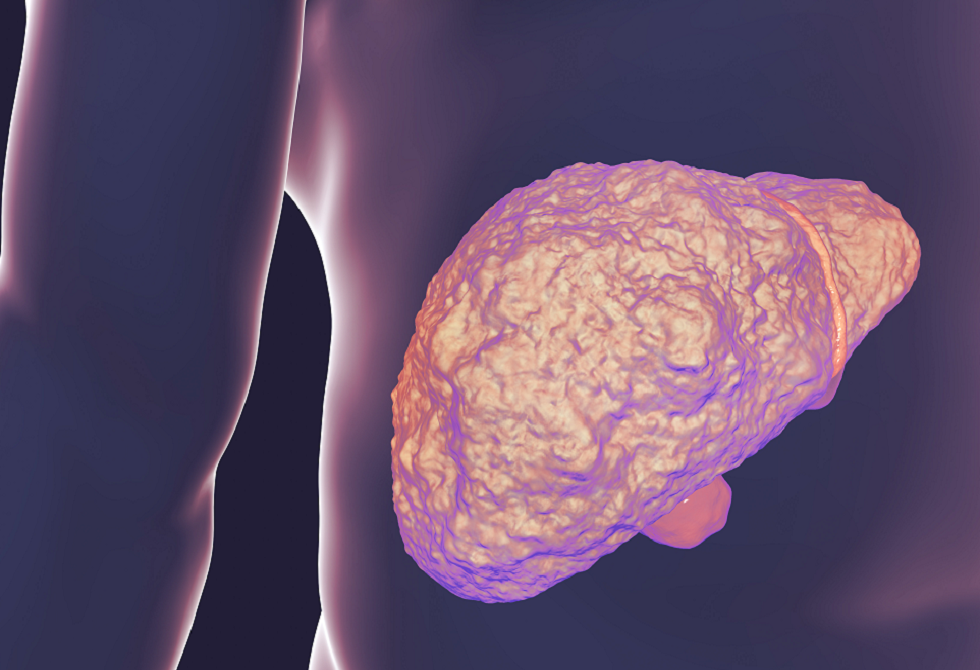

دور الكوليسترول في تدهور صحة الكبد

أظهر باحثون أن بلورات الكوليسترول في الكبد قد تؤدي إلى تصلبه في مرحلة مبكرة لدى المصابين بمرض الكبد الدهني المرتبط باضطراب التمثيل الغذائي (MASLD)، قبل ظهور التندب بفترة طويلة.

وقد تساعد هذه النتائج على تفسير تفاقم هذا النوع من أمراض الكبد نتيجة ارتفاع الكوليسترول، وتفتح فرصا جديدة للتشخيص والعلاج المبكرين.

وقالت الدكتورة ريبيكا جي. ويلز، أستاذة أمراض الجهاز الهضمي والكبد والمعدّة الرئيسية للدراسة: "لطالما شكّل التنبؤ بصحة الكبد، خصوصا لدى المصابين بمرض الكبد الدهني المرتبط باضطراب التمثيل الغذائي، تحديا كبيرا للأطباء، إذ إن حوالي ثلث سكان العالم لديهم تراكم دهون في الكبد، لكن نسبة قليلة منهم تصاب بأمراض كبدية خطيرة".

وأضافت أن الكشف عن بلورات الكوليسترول وتطوير طريقة سهلة للكشف عنها قد يساعد الأطباء على تحديد المرضى الأكثر عرضة لخطر الإصابة بأمراض كبدية حادة، ما يتيح التدخل المبكر عبر تشجيع العادات الغذائية الصحية أو مراقبة المرضى وتقديم العلاج قبل حدوث أضرار جسيمة.

تراكم الدهون في الكبد وخطورته

يحدث MASLD عندما تتراكم الدهون الزائدة في الكبد. وفي بعض الحالات، قد يحتاج المرضى إلى زراعة كبد أو يصابون بسرطان الكبد. ويرتبط تراكم الدهون بالسمنة ومقاومة الأنسولين وداء السكري من النوع الثاني، وغالبا ما يترافق مع سوء التغذية، بينما يلعب الاستعداد الوراثي دورا لدى بعض الأفراد.

وفي المختبر، أعطى فريق البحث من كلية بيرلمان للطب بجامعة بنسلفانيا، الفئران نظاما غذائيا غنيا بالدهون والكوليسترول أو نظاما غنيا بالدهون فقط. وأدى كلا النظامين إلى تشحم الكبد، أي تراكم الدهون في خلايا الكبد. لكن الفئران التي تناولت نظاما غنيا بالدهون والكوليسترول طورت بلورات في أكبادها، وكانت أكبادها أكثر صلابة مقارنة بالفئران الأخرى. ومن الجدير بالذكر أن قياس البلورات كان ممكنا فقط عبر الخزعة الجراحية.

بلورات الكوليسترول وعلاجات محتملة

أظهرت الدراسة أن بلورات الكوليسترول تصلّب أنسجة الكبد وتخلق بيئة تهيئ لمزيد من التندب. وقد تمكن الباحثون من عكس تصلب الكبد عبر إزالة البلورات في الفئران، رغم أن الطريقة لم تُطبق على البشر بعد.

وتظل هناك تحديات أمام التطبيق السريري، إذ لا يمكن قياس البلورات إلا بالخزعة، ما يحتم تطوير طريقة دقيقة وغير جراحية لتحديد المرضى الأكثر عرضة لخطر تلف الكبد.

وعلى الرغم من أن الستاتينات معروفة بقدرتها على خفض الكوليسترول في الدم، يأمل الباحثون في أن تساعد هذه الأدوية أو تدخلات أخرى متاحة على معالجة بلورات الكوليسترول في الكبد في المستقبل.

نشرت الدراسة في وقائع الأكاديمية الوطنية للعلوم.

المصدر: ميديكال إكسبريس